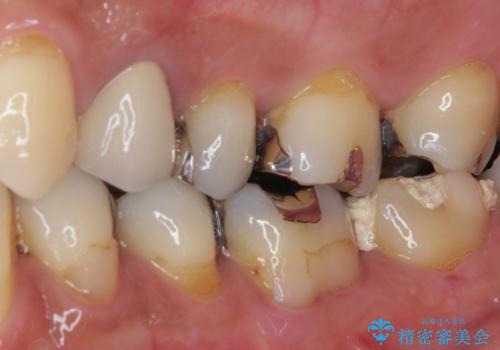

歯質の欠損が大きいため、処置後はオールセラミッククラウンにて補綴治療を行うこととしました。

神経組織を部分的に除去することが分かっていたため、ラバーダムなどの環境を整え、無菌的環境下にて処置を進めて行きました。

虫歯は深くまで進行しており、歯冠部の神経から出血が認められました。神経を部分的に除去したところ出血が治まったので、生体親和性の非常に高いセメントにて充填し、仮封をしました。